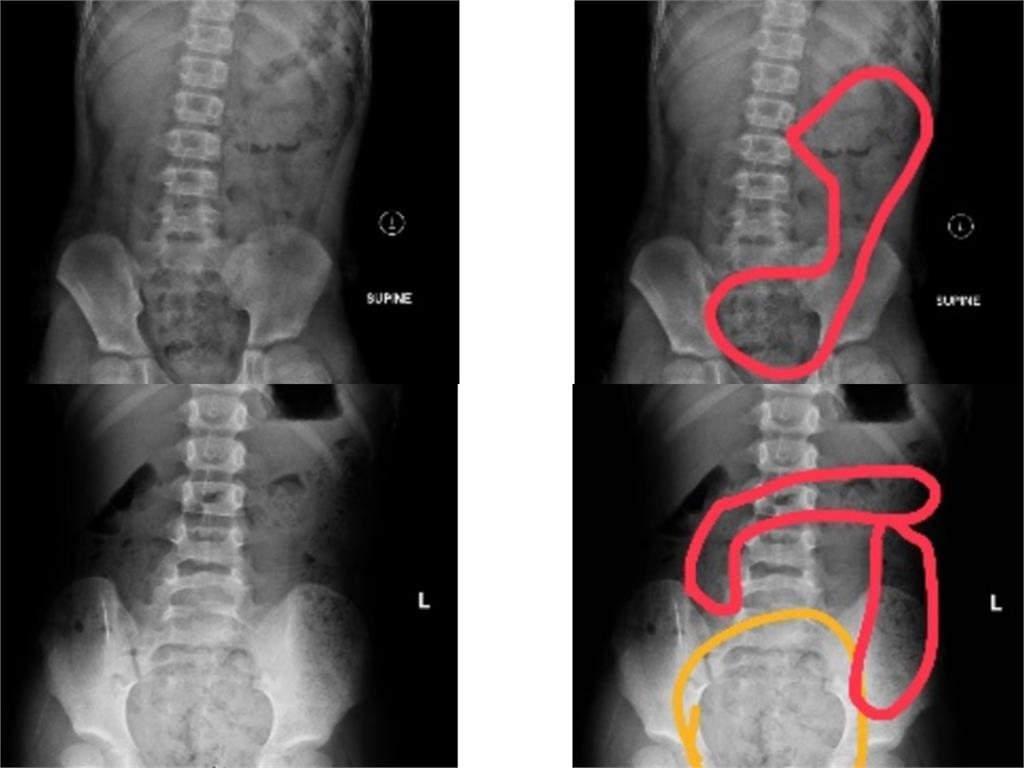

近日有兩名兒童因嚴重便秘送醫。一名11歲小五男童出現腹痛、冒冷汗、嘴唇發紫與手腳冰冷等症狀,被家人送急診。診斷後發現是嚴重便秘,在灌腸後排出大量糞便,症狀隨即緩解。男童家長表示,孩子習慣邊上廁所邊滑手機,常被催促後才從廁所出來,導致排便不完全。相同病例的還有一名6歲女童,因腹痛哭叫、腹部異常膨脹才就醫,X光檢查後,發現是因腸道內糞便堆積。女童母親也說,女兒上小學後不敢請假上廁所,導致長時間憋便。

一名11歲小五男童因出現腹痛、冒冷汗、嘴唇發紫與手腳冰冷等症狀,被家人緊急送去急診,醫生診斷為嚴重便祕導致。然而,在灌腸後排出大量糞便,症狀隨即緩解。男童母親透露,自家小孩習慣邊上廁所邊滑手機,所以每次時間過長就會被催促,因此男童總是匆忙出廁所,自己也不知道有沒有上出來或上乾淨。收治病例的阮綜合醫院急診兒科主治醫師蕭宇超指出,近期有多例兒童便秘病例,一名6歲女童則因肚子痛而哭叫,加上腹部異常膨脹才被家長送醫治療,經過X光檢查後,發現腸道內有糞便堆積。女童母親透露,因女兒上小學後,還沒熟悉上課節奏,就算便意來了,也不敢說要上廁所,長時間累積導致情況越來越嚴重才掛急診。